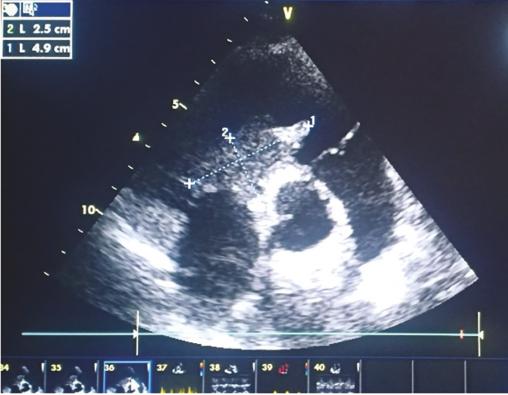

Cet homme de 21 ans consultait pour des hémoptysies. Il avait comme antécédent une aphtose bipolaire. L’électrocardiogramme était en rythme sinusal et l’échocardiographie (fig. 1 ) montrait un énorme thrombus du ventricule droit et de la veine cave inférieure. Sur l’angiotomodensitométrie thoracique (fig. 2 ), on notait de multiples anévrismes des artères pulmonaires. Le diagnostic de maladie de Behçet était retenu devant la thrombose intracardiaque, l’antécédent d’aphtose bipolaire, une uvéite antérieure et le test de sensibilité cutanée. Le patient était mis sous corticothérapie, colchicine et anticoagulation avec une bonne évolution clinique et la persistance du thrombus cardiaque. Le malade était adressé pour une thrombectomie chirurgicale.